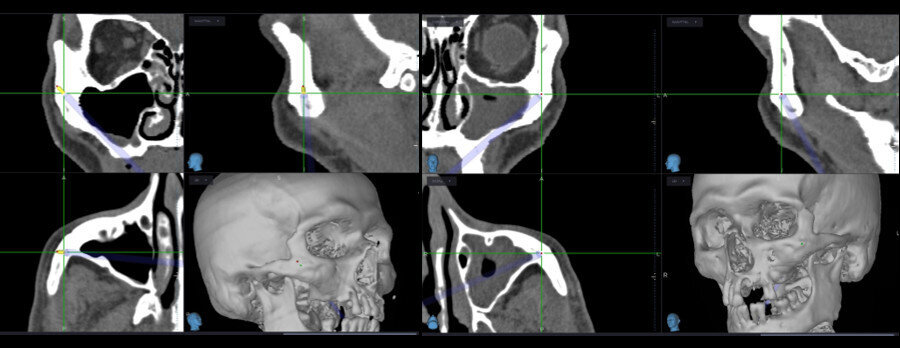

Figs. 10a–c: Final CT scan with cross-sectional (a), coronal (b) and sagittal (c) views.

The images provided intra-operatively and in real time are of great definition and highly informative. The system also allows the introduction of a colour code to establish safety limits with respect to the length and diameter of the zygomatic implants. Navigation can also be used for other conventional implants (Fig. 9). After completion of the surgery, a new high-definition CT scan was performed to check the final positions of the two zygomatic implants placed in the posterior of the maxilla and the four conventional implants placed in the anterior sector of the maxilla (Fig. 10).